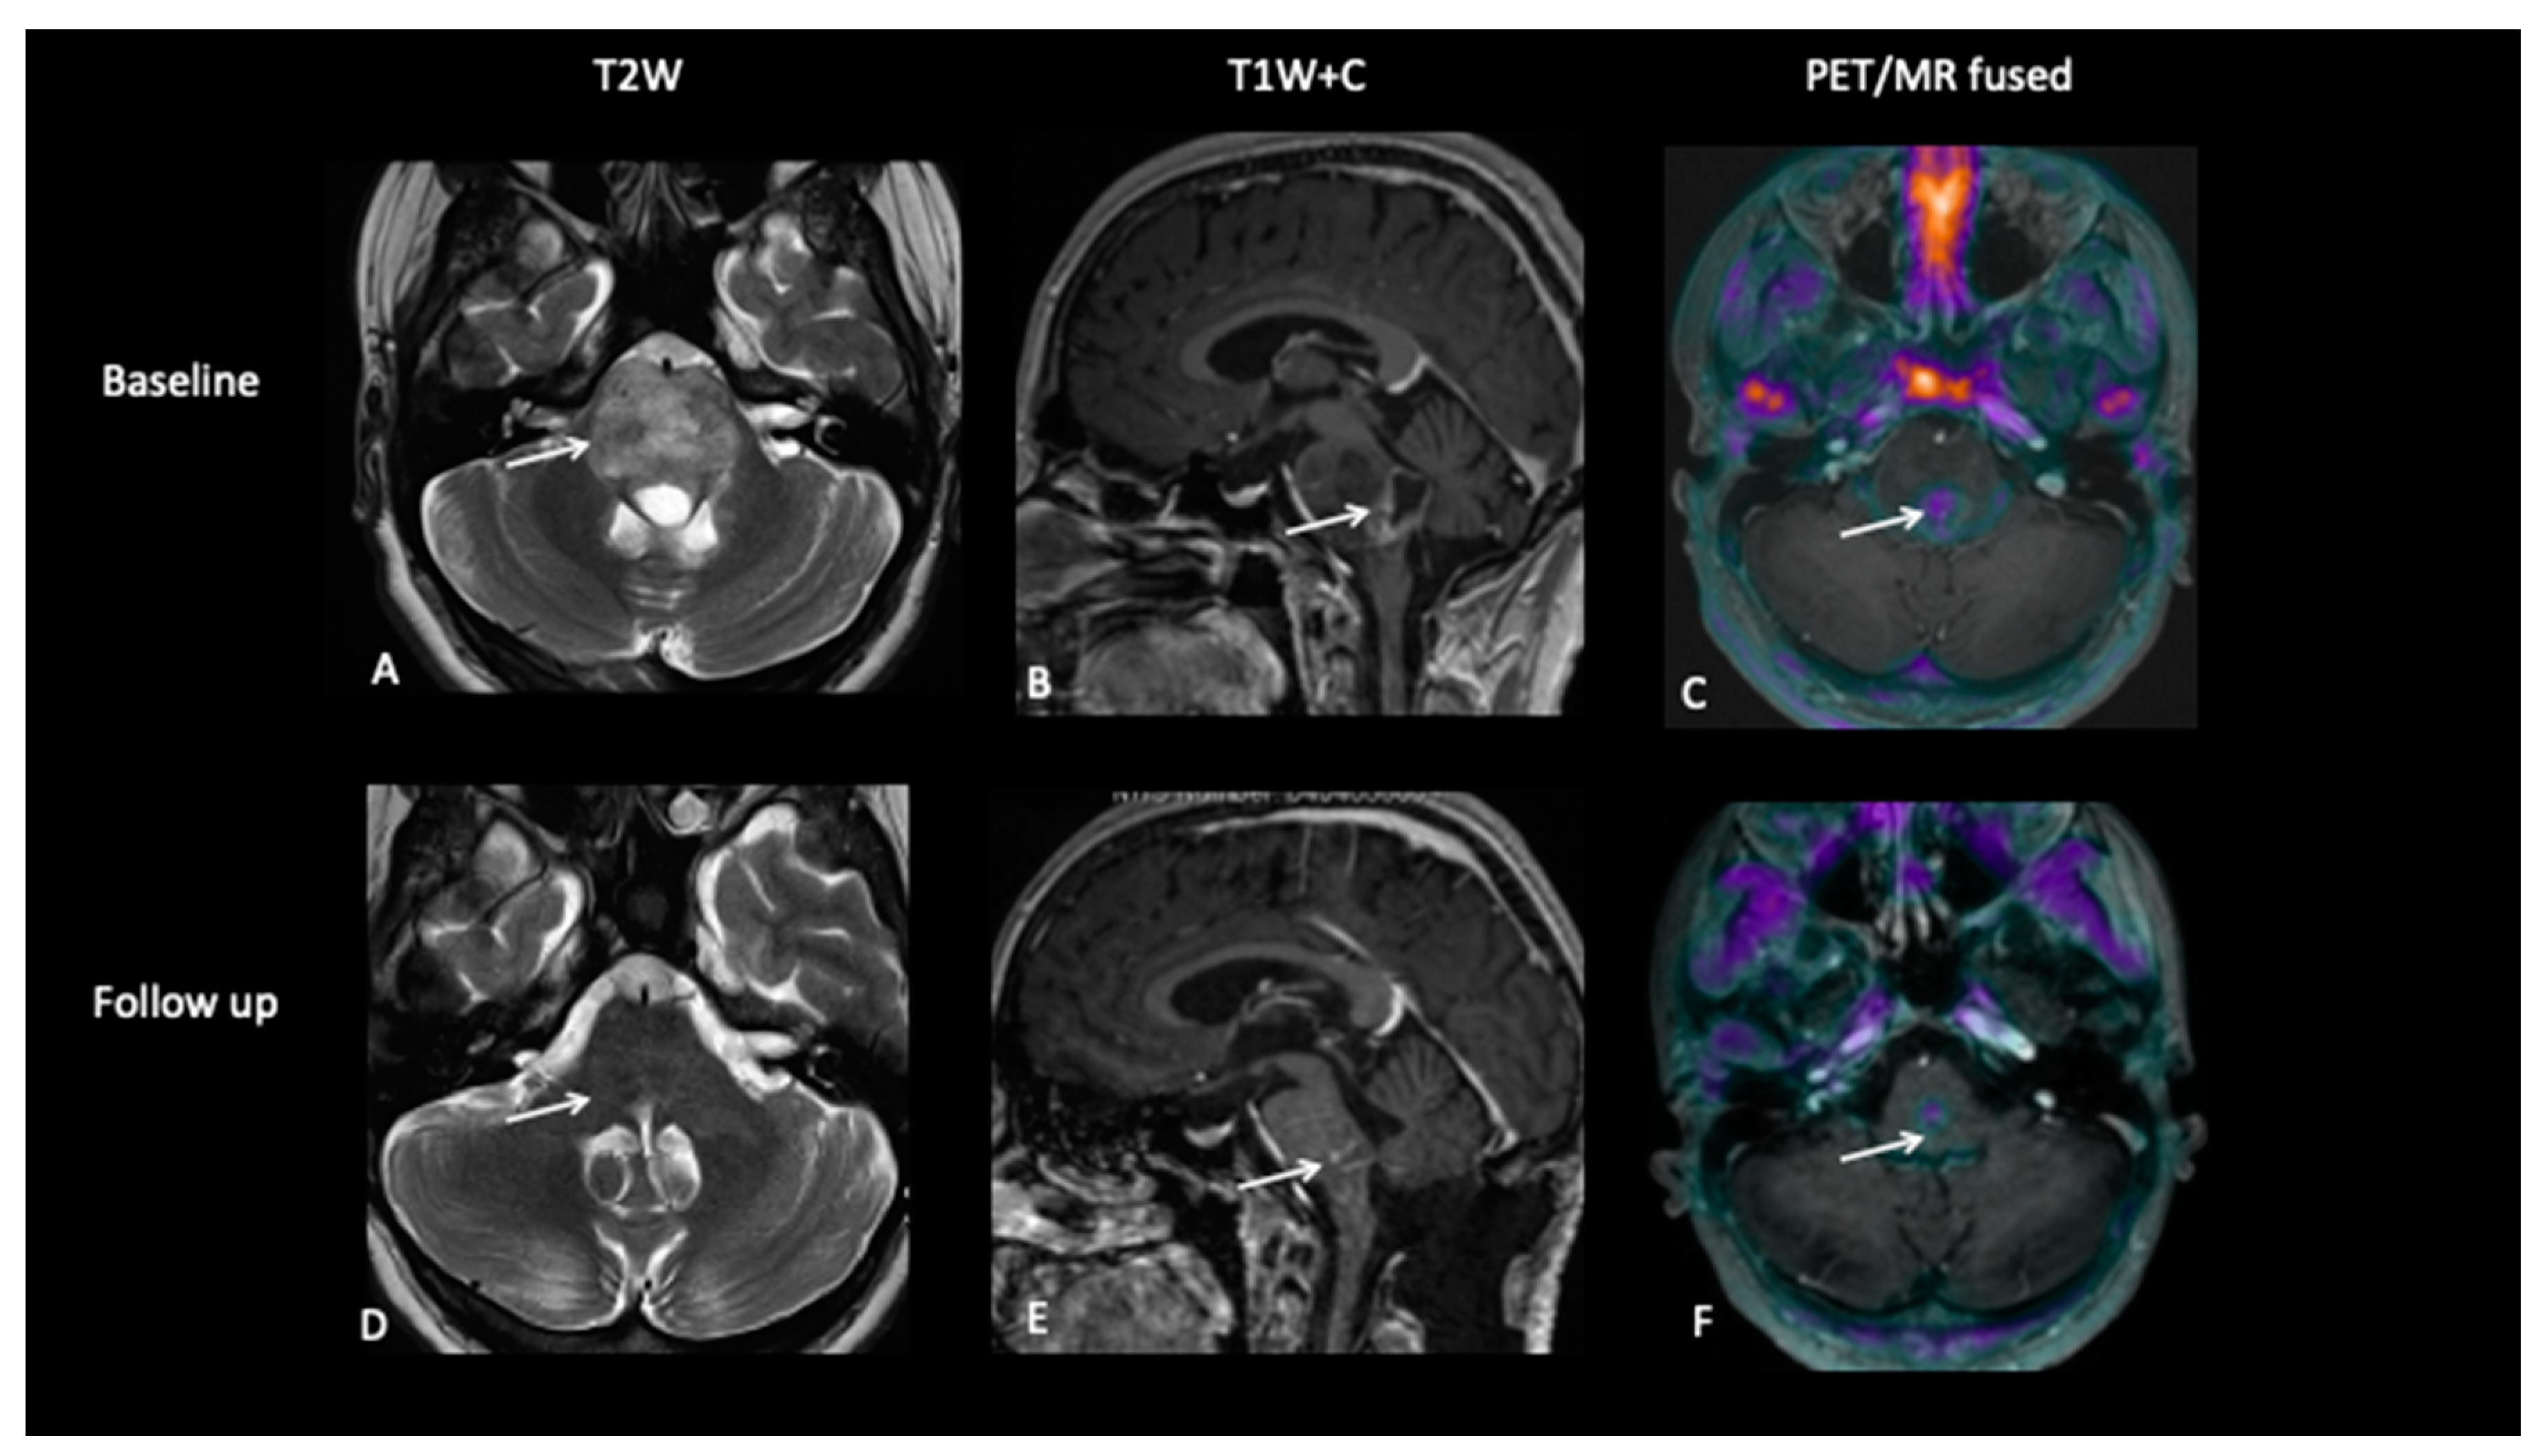

At baseline, there is a large pontine tumour (A) with a dorsally exophytic enhancing component (B), which shows FCho avidity on the PET/MR fused image (C). Follow-up imaging demonstrates residual dorsal enhancement (D,E), but FCho confirms no avidity (F) consistent with complete metabolic response.

- Patient 2: Early Response Assessment

A 13-year-old female with a large tumour involving left thalamus and basal ganglia, infiltrating into the adjacent white matter, insular cortex and left aspect of the upper brain stem underwent a biopsy of the thalamic component, which confirmed high-grade astrocytoma with a mutation of the variant H3.3 gene. An early response assessment scan 6 weeks after completion of chemoradiotherapy demonstrated no residual enhancement in the tumour, but FDOPA PET showed residual tracer distribution consistent with residual metabolically active disease (Figure 5).

Figure 5.

At baseline, there is non-enhancing tumour involving the left basal ganglia (A,B) with 8F-fluorocholine (FCho) and 18fluoro-L-phenylalanine (FDOPA) avidity (C). Follow-up imaging shows residual non-enhancing tumour (D,E) reported as stable disease, but FDOPA PET demonstrates reduced uptake (F) consistent with metabolic partial response.

- Patient 3: Tumour Progression Versus Pseudoprogression

A 5-year-old female with diffuse midline glioma (DMG) presented with a short history of headaches, difficulty in walking and double vision. Radiology at diagnosis was consistent with diffuse intrinsic pontine glioma (DIPG). She commenced on 6 week course of focal radiotherapy (RT) to the pontine tumour with good initial response (Figure 6). The patient then went to Mexico for a form of targeted treatment and after four cycles developed clinical signs of disease progression. Whilst follow-up MRI demonstrated increased enhancement and raised the possibility of pseudoprogression, FDOPA PET demonstrated areas of avidity confirming clear progression.

Figure 6.

Baseline imaging demonstrates large pontine tumour (A) with focus of enhancement (B). Follow-up imaging demonstrated a large heterogenous right hemipontine mass (C,D) suspicious for tumour progression, but FDOPA (E) did not show increased uptake (white arrow) and was suggestive of pseudoprogression. However, FDOPA did show increased avidity in the left cerebellar hemisphere (red arrow) confirming non-enhancing tumour progression at that site.